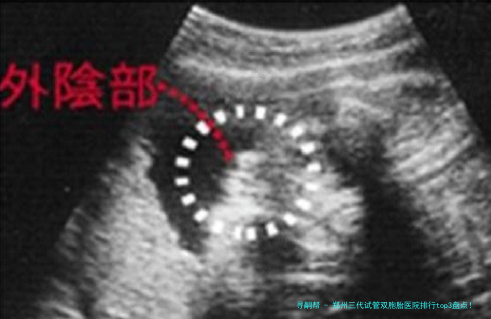

郑州三代试管双胞胎医院排行top3盘点!2025年新生双胎费用、、技术对比及选择指南全攻略

当"一次性儿女双全"的梦想超过三代试管婴儿技术,无数夫妻既期待又迷茫——在郑州,哪些医院真正擅长三代试管双胞胎技术?到底有多高?费用会不会是天价?今日,我准备结合2025年新数据,给你揭秘郑州三代试管双生子医院排行前三强,从技术原理到医院选择,帮助你做出理智决策!💡